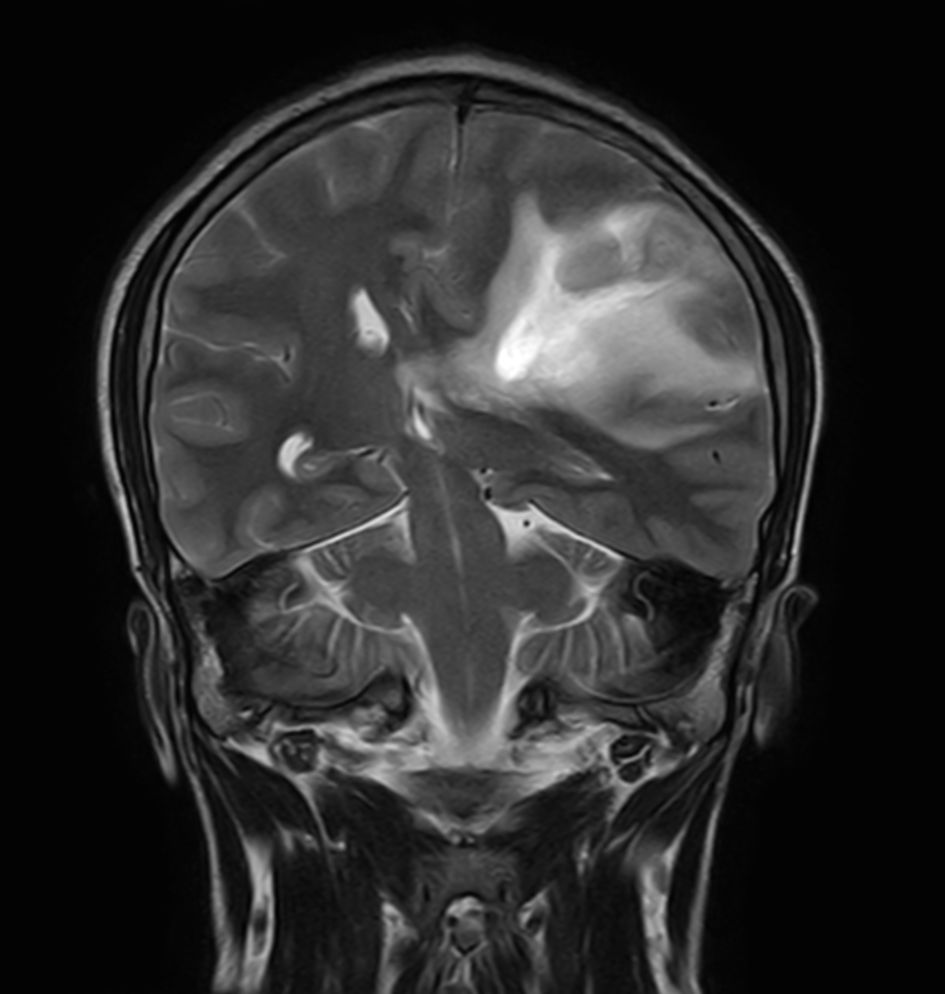

Pediatric Brain with hemorrhagic mass

Pediatric patient with a hemorrhagic mass in the brain